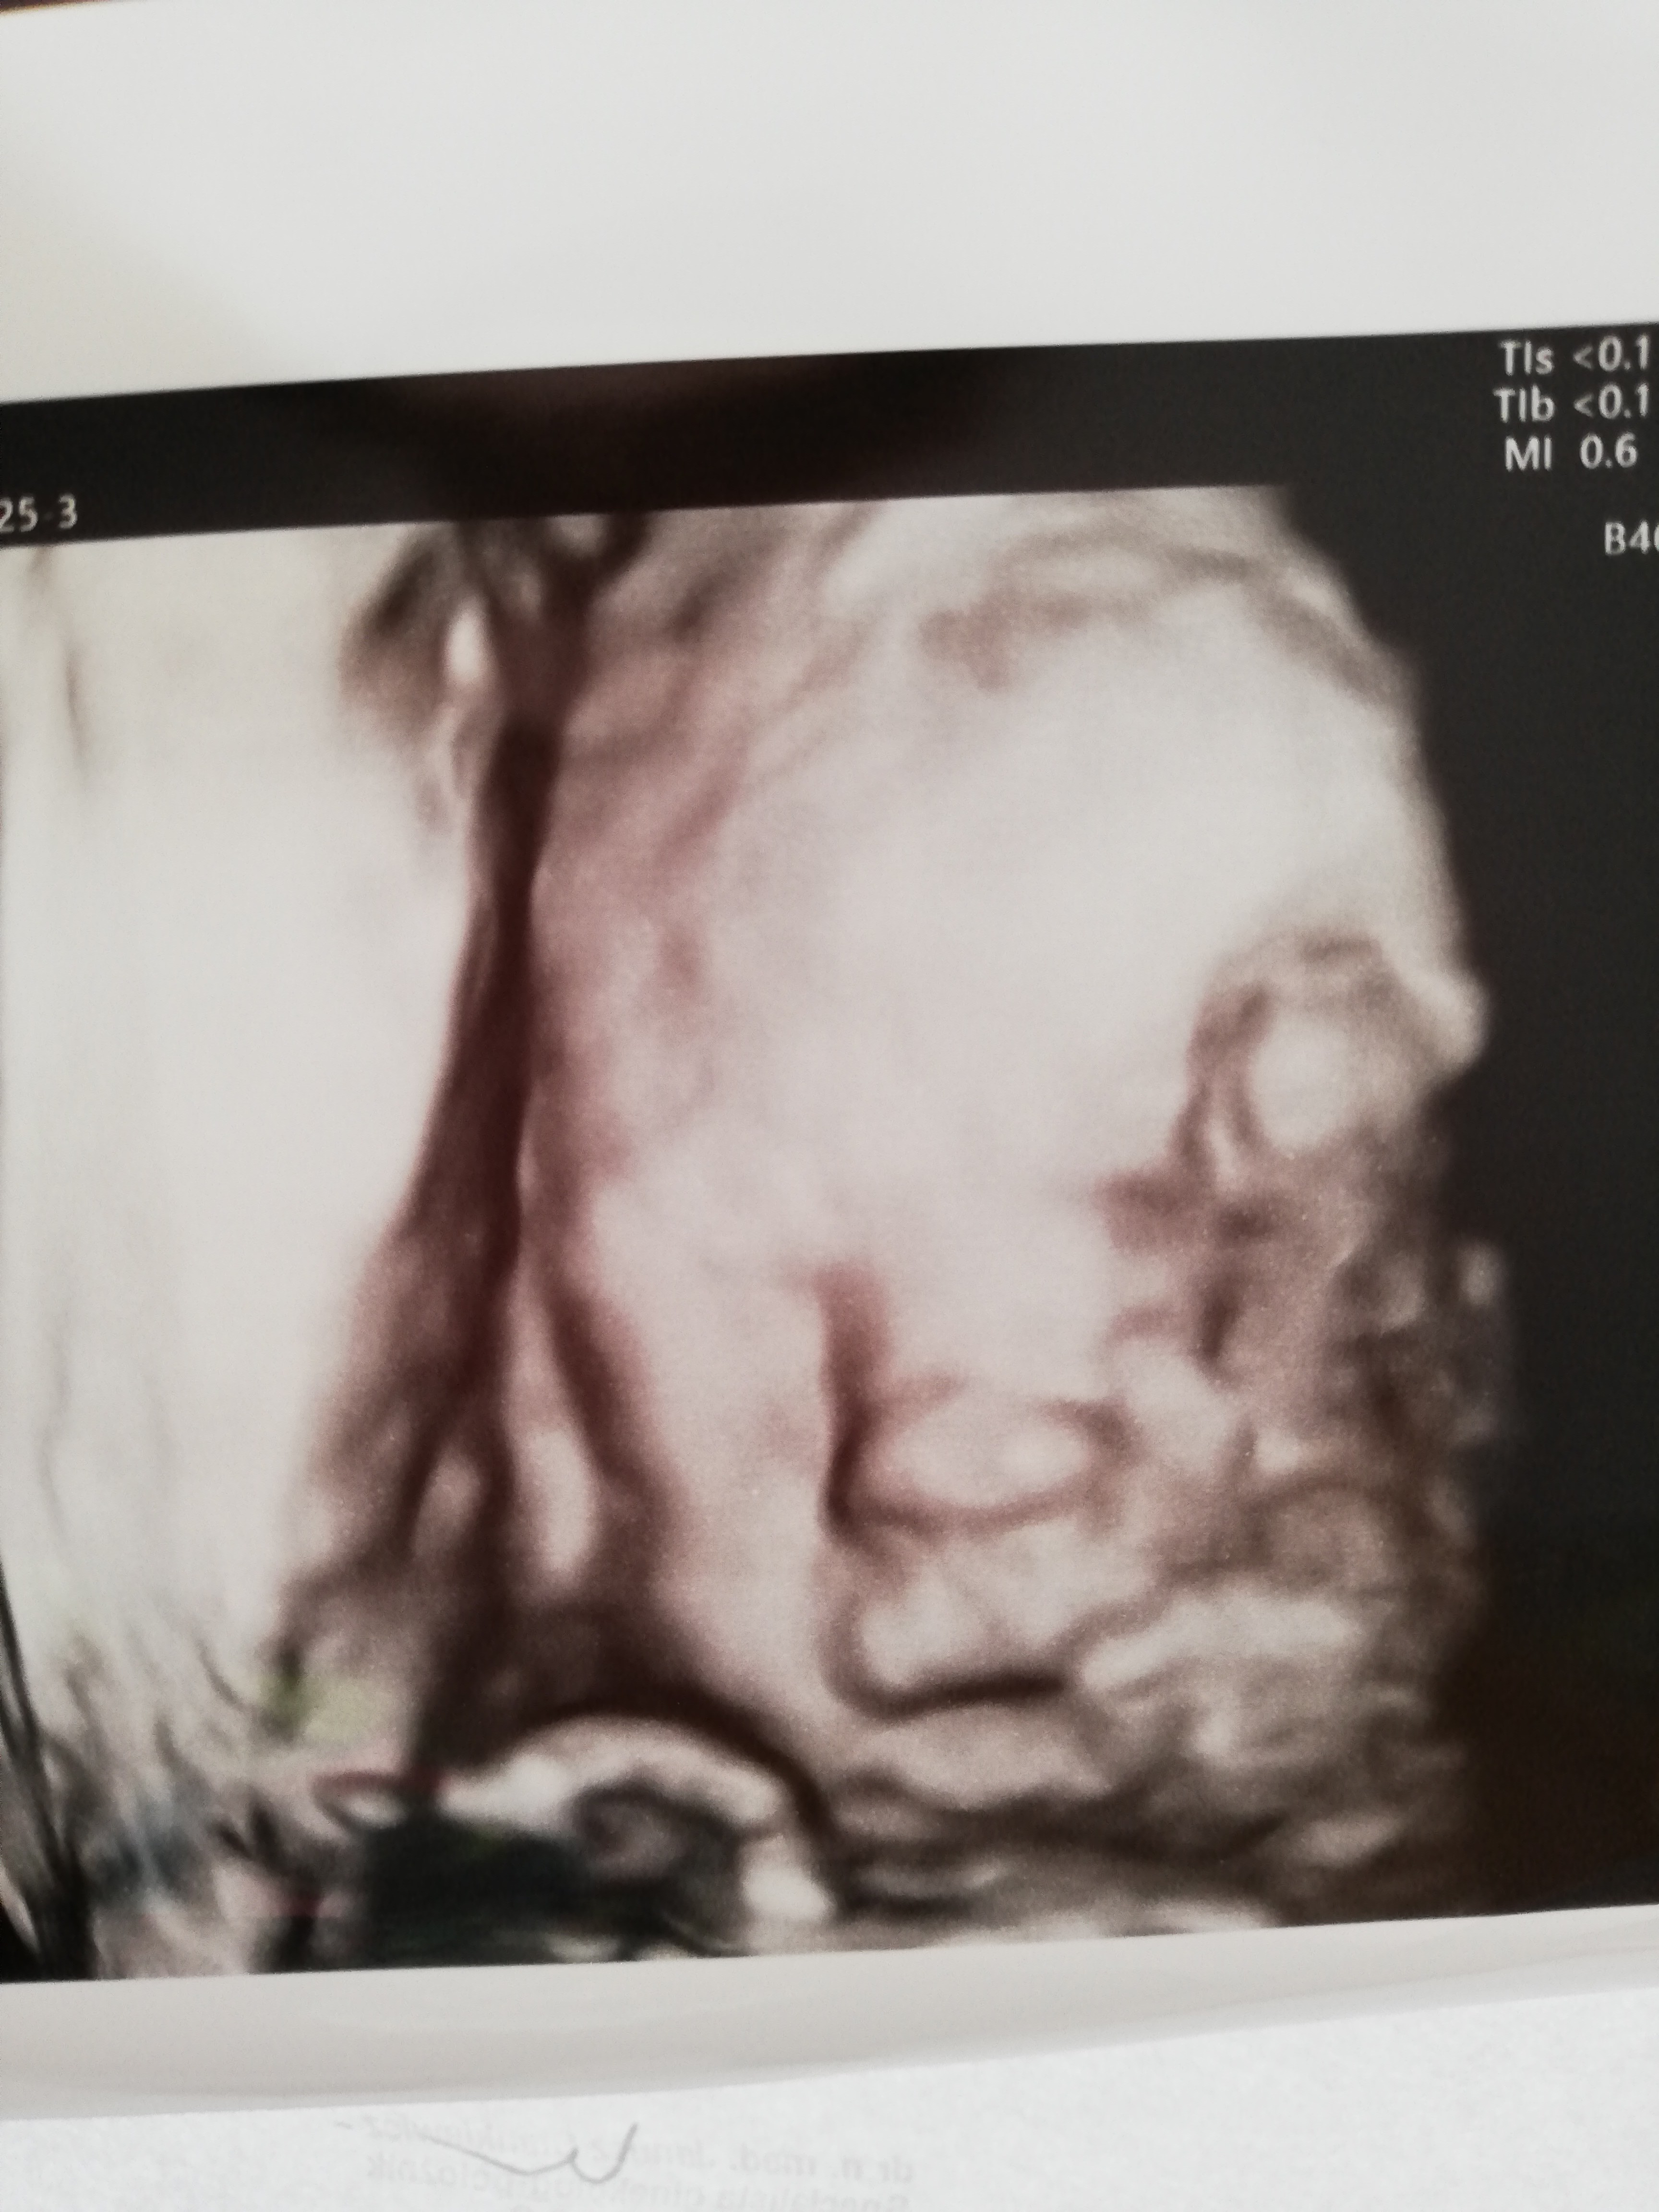

A ja tutaj Wam przedstawiam mojego Andrzeja 🥰 zaczęliśmy 20 tc 😍

Papa plus usg.